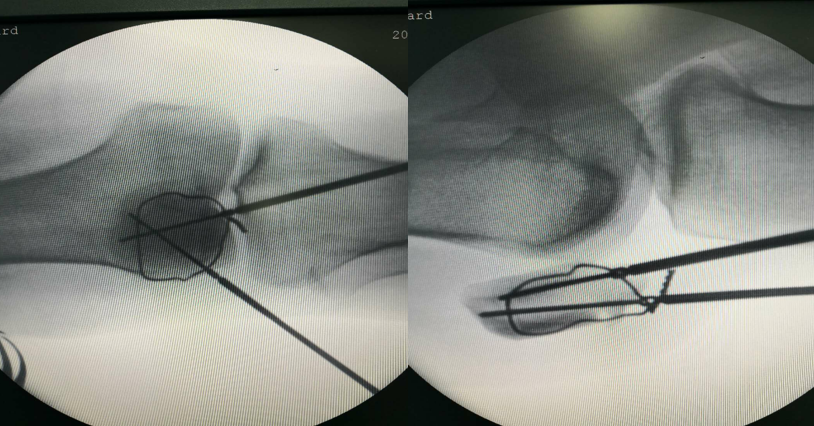

先扪及髌骨上下极及断端,用电钻于髌骨上极打一骨洞

利用腰穿针带过钢丝

再用利用腰穿针引导钢丝

收紧钢丝打结使其骨折端复位,透视发现复位欠佳

继续收紧钢丝,骨折复位,剪断钢丝

将钢丝埋于深处

由下方两钢丝口打入两髌骨

术后切口照片(无需缝合)

病房照(创口小,仅4个。最大的内下口约4MM)